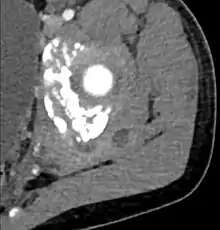

![]() أشعة مقطعية محورية على مستوى T1 توضح التهاب العضلات التقيحي الناتج عن الاصابة بالبكتيريا المكورة العنقودية الذهبية التي تستجيب للميثيسلين. ]] | |

غالبًا ما تتسبب البكتيريا المكورة العنقودية الذهبية في التهاب العضلات التقيُّحي.[5] يمكن أن تؤثر العدوى على أي عضلة هيكلية، ولكنها غالبًا ما تصيب مجموعات العضلات الكبيرة مثل عضلات الفخذ أو العضلات الألوية.[4][6][7]